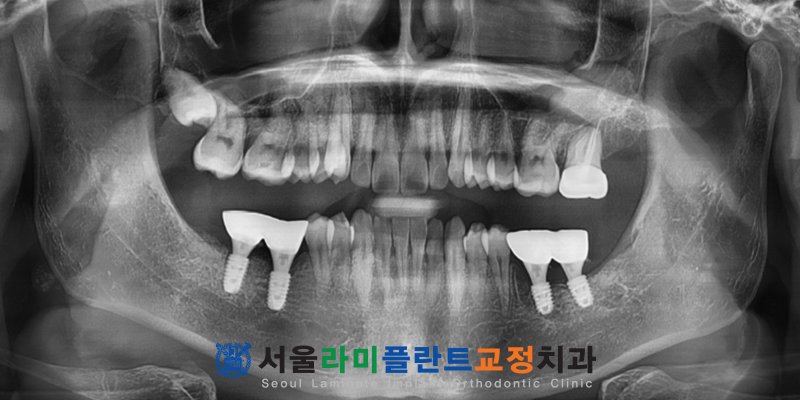

이어서 진행된 두 번째 수면에서는

오른쪽 부위의 발치와 임플란트

식립 과정을 마무리하였습니다.

이 기간 동안 총 6개의 치아를 발치하고

4개의 임플란트를 성공적으로 식립하였으며

1개 치아의 신경치료와

크라운 수복까지 마쳤습니다.